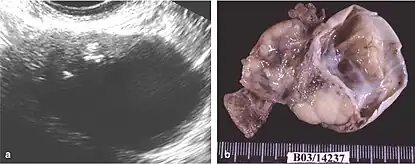

Mature cystic teratoma (MCT), affecting women in 10–20% of cases during their lifetime, is characterized by benign mature cystic teratomas—an intriguing subject in gynecological pathology.[8][3] These non-cancerous tumors, originating from at least two embryonic germ cell layers, exhibit a complex interplay of developmental pathways, stemming from singular germ cells or the complexities of meiosis I and II failure.[9][10] Internally lined with squamous epithelium and externally connected to the ovarian stroma, mature cystic teratomas contain diverse fluids such as sebaceous, serous, or mucinous.

Although the majority of MCT cases are non-malignant, approximately 0.17-2% may undergo malignant transformation, with squamous cell carcinoma being the most prevalent, constituting 80% of such transformations.[11] The clinical presentation of oSCC development within MCT lacks specificity, often resulting in the inadvertent discovery of early-stage tumors during routine examinations or postoperative assessments. In advanced cases, patients may exhibit palpable masses, abdominal swelling, and pain, potentially leading to acute abdominal complications due to tumor involvement.[10][12][4]

The difficulty in screening for SCC revolves around the creation of effective strategies with a positive predictive value. The timing aspect is crucial due to the lack of a specific timeframe for the onset of invasive disease or the interval stage between stage I and stage III carcinomas.[17] Ultrasound screening provides a detailed view of the ovaries, identifying morphologic changes as potential signs of malignancy. Key diagnostic factors include the presence of abnormalities, ovarian size, blood flow, and abdominal/pelvic fluid. The persistence of abnormalities after four to six weeks may decrease the occurrence of false positives. Screening protocols, often based on morphologic indices, utilize transvaginal ultrasound findings like cyst wall structure, septation, papillary projections, echogenicity, and ovarian volume to effectively detect malignancy.[17]